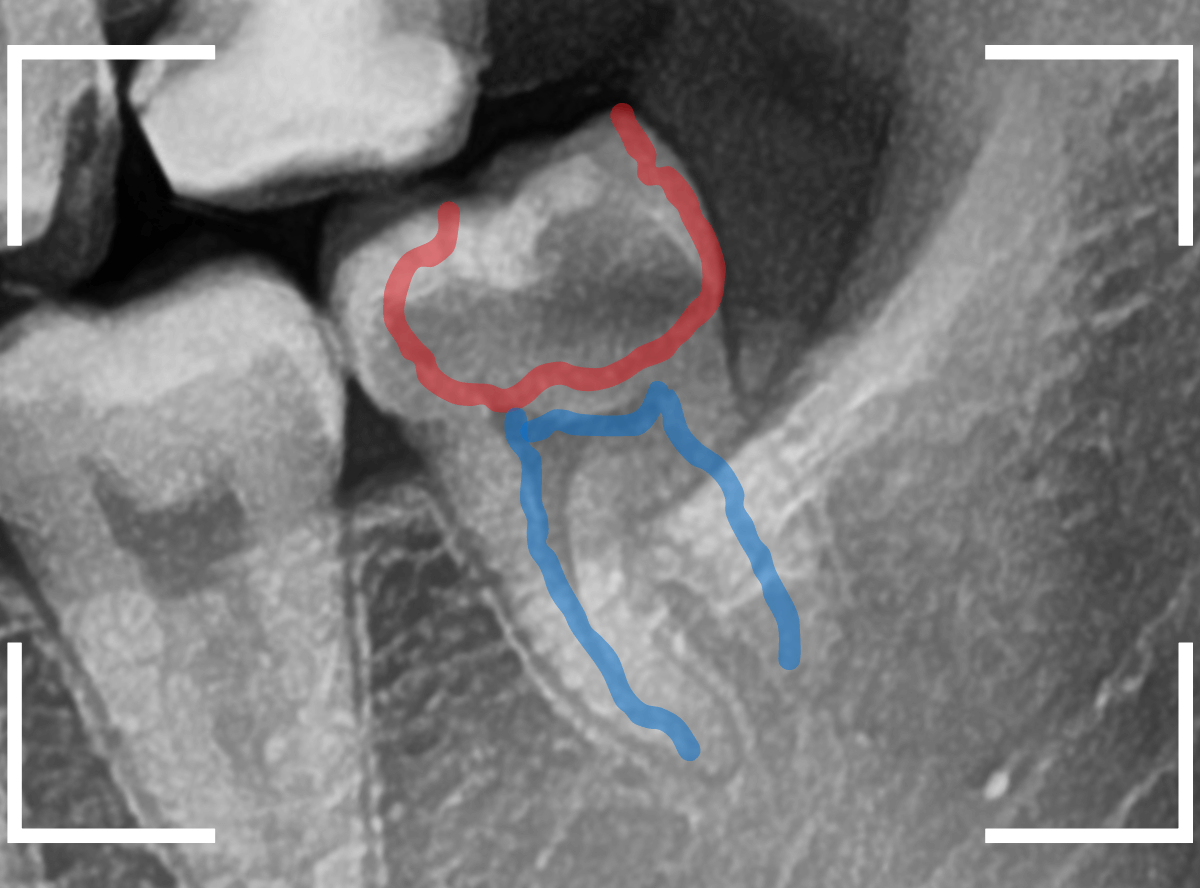

ここでは、比較的簡単なおやしらずの抜歯の例を中心にご紹介します。

このようなおやしらず、あなたはありませんか?